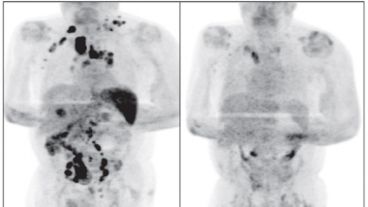

El diagnóstico era un linfoma de Hodgkin clásico en estadio III, trastorno que afecta a áreas ganglionares localizadas a ambos lados del diafragma o por encima de él y en el bazo.

Cuatro meses después la inflamación de los ganglios se había reducido y una exploración por tomografía reveló una remisión generalizada del linfoma, a pesar de que no se le administró corticosteroides ni inmunoquimioterapia, aclara el informe.

La hipótesis es que la infección por sars-cov-2 desencadenó una respuesta inmunitaria antitumoral.

Según los autores que dieron a conocer este caso, la hipótesis es que la infección por sars-cov-2 desencadenó una respuesta inmunitaria antitumoral, algo que, según señalan los especialistas, se ha descrito con otras infecciones en el contexto del linfoma no Hodgkin de alto grado.